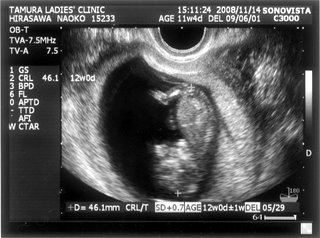

そして、経膣エコーで赤ちゃんがいるか見ました

カーテン越しに先生第一声。

先生「もう大きいよ。」

私「…!?!???」

少しカーテンを開けてモニターを見せてもらってビックリ

先生がピピピと計算してくれて予定日は2009年6月1日。

次の日から12週つまり4か月に入るということでした。